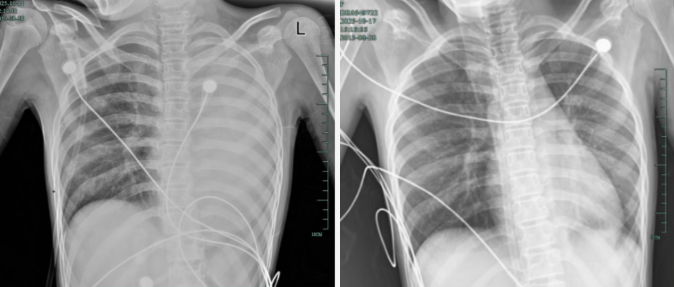

治疗前,左肺呈“白肺”状态;治疗后,“白肺”被吸收,心脏边缘清晰可见

入院后,她很快出现呼吸急促、胸闷胸痛,体温38.5℃,只能靠5L/min的面罩吸氧维持血氧,胸片显示左肺已完全呈“白肺”改变,肺部炎症进展迅猛。

后续检查发现,引发她此次感染的是毒力极强的铜绿假单胞菌,多发生在免疫功能低下人群。经过精准抗感染、祛痰、抗炎等系列治疗,孩子逐渐康复,已顺利出院。庆幸的是,笑笑的“白肺”基本吸收,恢复如常,没有留下严重的并发症。